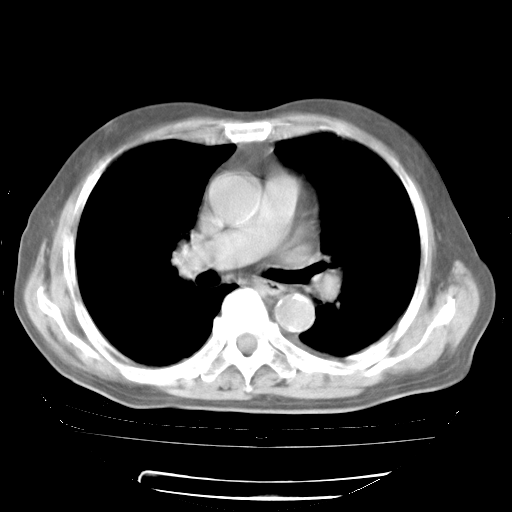

4月28日肺部CT——再次出现类似去年5月9日——透光度降低,“间质性”改变。